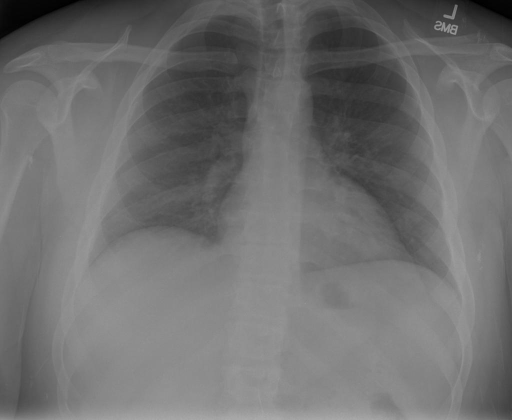

## 本文贡献  - 借助ChatGPT以及公开的数据集,我们构造了一个`X光影像-诊断报告`对的医学多模态数据集; - 我们将构建的中文胸部X光片诊断数据集在[VisualGLM-6B](https://github.com/THUDM/VisualGLM-6B)进行微调训练,并开放了部分训练权重用于学术研究; ## 数据集 - [MIMIC-CXR](https://physionet.org/content/mimic-cxr-jpg/2.0.0/)是一个公开可用的胸部X光片数据集,包括377,110张图像和227,827个相关报告。 - [OpenI](https://openi.nlm.nih.gov/faq#collection)是一个来自印第安纳大学医院的胸部X光片数据集,包括6,459张图像和3,955个报告。 在上述工作中,报告信息都为非结构化的,不利于科学研究。为了生成合理的医学报告,我们对两个数据集进行了预处理,并最终得到了可以用于训练的**英文报告**。除此之外,为了更好的支持中文社区发展,借助ChatGPT的能力,我们将英文报告进行了中文翻译,并最终形成了可用于训练的数据集。 |数据集|数量|下载链接| |:-|:-|:-| |MIMIC-CXR-zh|-|-| |OpenI-zh|6,423|[诊疗报告(英文)](./data/openi-en.json)、[诊疗报告(中文)](./data/Xray/openi-zh.json) 、[X光影像](https://pan.baidu.com/s/13GBsDMKf6xBZBSHpoWH_EA?pwd=k9sh)| ## 快速上手 1. 安装环境 ```bash # 安装依赖 pip install -r requirements.txt # 国内换源安装依赖 pip install -i https://mirrors.aliyun.com/pypi/simple/ -r requirements.txt ``` 此时默认会安装`deepspeed`库(支持`sat`库训练),此库对于模型推理并非必要,同时部分`Windows`环境安装此库时会遇到问题。 如果想绕过`deepspeed`安装,我们可以将命令改为: ```bash # 安装依赖 pip install -i https://mirrors.aliyun.com/pypi/simple/ -r requirements_wo_ds.txt # 安装SwissArmyTransformer pip install -i https://mirrors.aliyun.com/pypi/simple/ --no-deps "SwissArmyTransformer>=0.3.6" ``` 2. 模型推理 CLI推理: ```python python cli_demo.py --from_pretrained checkpoints/finetune-XrayGLM-05-25-01-04 --prompt_zh '详细描述这张胸部X光片的诊断结果' ``` 更多[参数](https://github.com/WangRongsheng/XrayGLM/blob/main/cli_demo.py#L16) ## 效果展示 影像诊断: |X光影像|诊疗报告(医生)|XrayGLM| |:-|:-|:-| ||根据X射线图像,心脏大小正常,肺部看起来很清晰。已经排除了肺炎、积液、水肿、气胸、腺病、结节或肿块的存在。该发现表明一切正常。换句话说,总体印象是胸部正常。|X光片显示,心脏大小正常。肺部没有气胸或胸腔积液的证据。骨骼结构看起来没有任何异常。总的来说,X光片表明没有发现急性心肺疾病的迹象。| ||X光图片显示没有扭曲的区域、可疑的骨质不透明度或胸腺积液。心脏大小轻微增大,但非常稳定。此外,没有气胸的证据,肺野也正常。总体来说,X光片显示没有急性心脏异常,但要注意轻微的心脏扩大。|X光片显示,心脏大小正常。肺部和纵隔轮廓清晰,没有气胸或胸腔积液的证据。骨骼结构完整,没有任何急性异常。| ||心影形态在正常范围内。没有急性骨质异常。有可能出现没有明显的吸水或肺实质状况的线索。没有大面积积液或气胸。有可能怀疑其有误吸或肺实质问题。为了确诊和治疗,可能需要进行适当的影像学随访。|心脏大小正常,肺部和纵隔轮廓清晰。没有急性异常或活动受限的证据。没有任何明显的气胸、胸腔积液或肺不张的迹象。此外,也没有发现任何局灶性骨质异常或其他急性疾病。| 多轮对话: |X光影像|诊疗报告(医生)| |:-|:-| ||右侧主动脉突出观察到。心脏大小正常。胸部未发现明显的肺气肿、胸膜积液或可疑的肺部病变。报告指出已知右侧主动脉情况正常。| ```bash >> X光影像路径:./data/Xray/861_1.png >> 用户:这是一张什么图? >> XrayGLM:这张图片显示的是一张肺部检查的X光片。 >> 用户:请描述这张胸部X光片的诊断结果 >> XrayGLM:心脏大小正常,肺部清晰。没有急性心肺疾病的证据。 >> 用户:是否存在肺气肿? >> XrayGLM:没有肺气肿。心脏大小正常,肺部清晰。没有发现急性心肺疾病的证据。 >> 用户:平时饮食该注意什么? >> XrayGLM:饮食应该健康,均衡。建议增加蛋白质的摄入量,因为蛋白质有助于维持肌肉和骨骼的健康。多食用蔬菜、水果、全谷物以及健康的脂肪来源如橄榄油、鱼类等可以帮助获得足够的维生素和矿物质。此外,避免过度饮酒或吸烟,这些习惯可能会对心脏健康产生负面影响。 ``` ## 未来展望 1. 模型的能力更多来源于数据的支持,`OpenI-zh`作为微调数据集,其数据量足以支持研究,在更广泛的任务和性能表现上,我们认为**在大规模数据集上预训练并在高质量少量数据集上微调是一种可行的方案**; 2. 普遍意义的理解上,视觉多模态模型=视觉模型+语言模型。除了需要关注视觉模型信息与语言模型输出的搭配外,还需要**额外关注到语言模型的加强,在人机的对话中,尤其是医疗语言模型的问答上,除了专业的医疗问题回答,带有人文情怀的有温度的回答更应该是我们追寻的目标**。 ## 项目致谢 1. [VisualGLM-6B](https://github.com/THUDM/VisualGLM-6B)为我们提供了基础的代码参考和实现; 2. [MiniGPT-4](https://github.com/Vision-CAIR/MiniGPT-4)为我们这个项目提供了研发思路; 3. ChatGPT生成了高质量的中文版X光检查报告以支持XrayGLM训练; 4. [gpt_academic](https://github.com/binary-husky/gpt_academic)为文档翻译提供了多线程加速; 5. [MedCLIP](https://github.com/RyanWangZf/MedCLIP) 、[BLIP2](https://huggingface.co/docs/transformers/main/model_doc/blip-2) 、[XrayGPT](https://github.com/mbzuai-oryx/XrayGPT) 等工作也有重大的参考意义;  这项工作由[澳门理工大学应用科学学院](https://www.mpu.edu.mo/esca/zh/index.php)硕士生[王荣胜](https://github.com/WangRongsheng) 、[段耀菲](https://github.com/IsBaSO4) 、[李俊蓉](https://github.com/lijunrong0815)完成,指导老师为檀韬副教授、[彭祥佑](http://www.patrickpang.net/)老师。 *特别鸣谢:[USTC-PhD Yongle Luo](https://github.com/kaixindelele) 提供了有3000美金的OpenAI账号,帮助我们完成大量的X光报告翻译工作 ## 免责声明 本项目相关资源仅供学术研究之用,严禁用于商业用途。使用涉及第三方代码的部分时,请严格遵循相应的开源协议。模型生成的内容受模型计算、随机性和量化精度损失等因素影响,本项目无法对其准确性作出保证。即使本项目模型输出符合医学事实,也不能被用作实际医学诊断的依据。对于模型输出的任何内容,本项目不承担任何法律责任,亦不对因使用相关资源和输出结果而可能产生的任何损失承担责任。 ## 项目引用 如果你使用了本项目的模型,数据或者代码,请声明引用: ```bash @misc{wang2023XrayGLM, title={XrayGLM: The first Chinese Medical Multimodal Model that Chest Radiographs Summarization}, author={Rongsheng Wang, Yaofei Duan, Junrong Li, Patrick Pang and Tao Tan}, year={2023}, publisher = {GitHub}, journal = {GitHub repository}, howpublished = {\url{https://github.com/WangRongsheng/XrayGLM}}, } ``` ## 使用许可 此存储库遵循[CC BY-NC-SA](https://creativecommons.org/licenses/by-nc-sa/4.0/) ,请参阅许可条款。